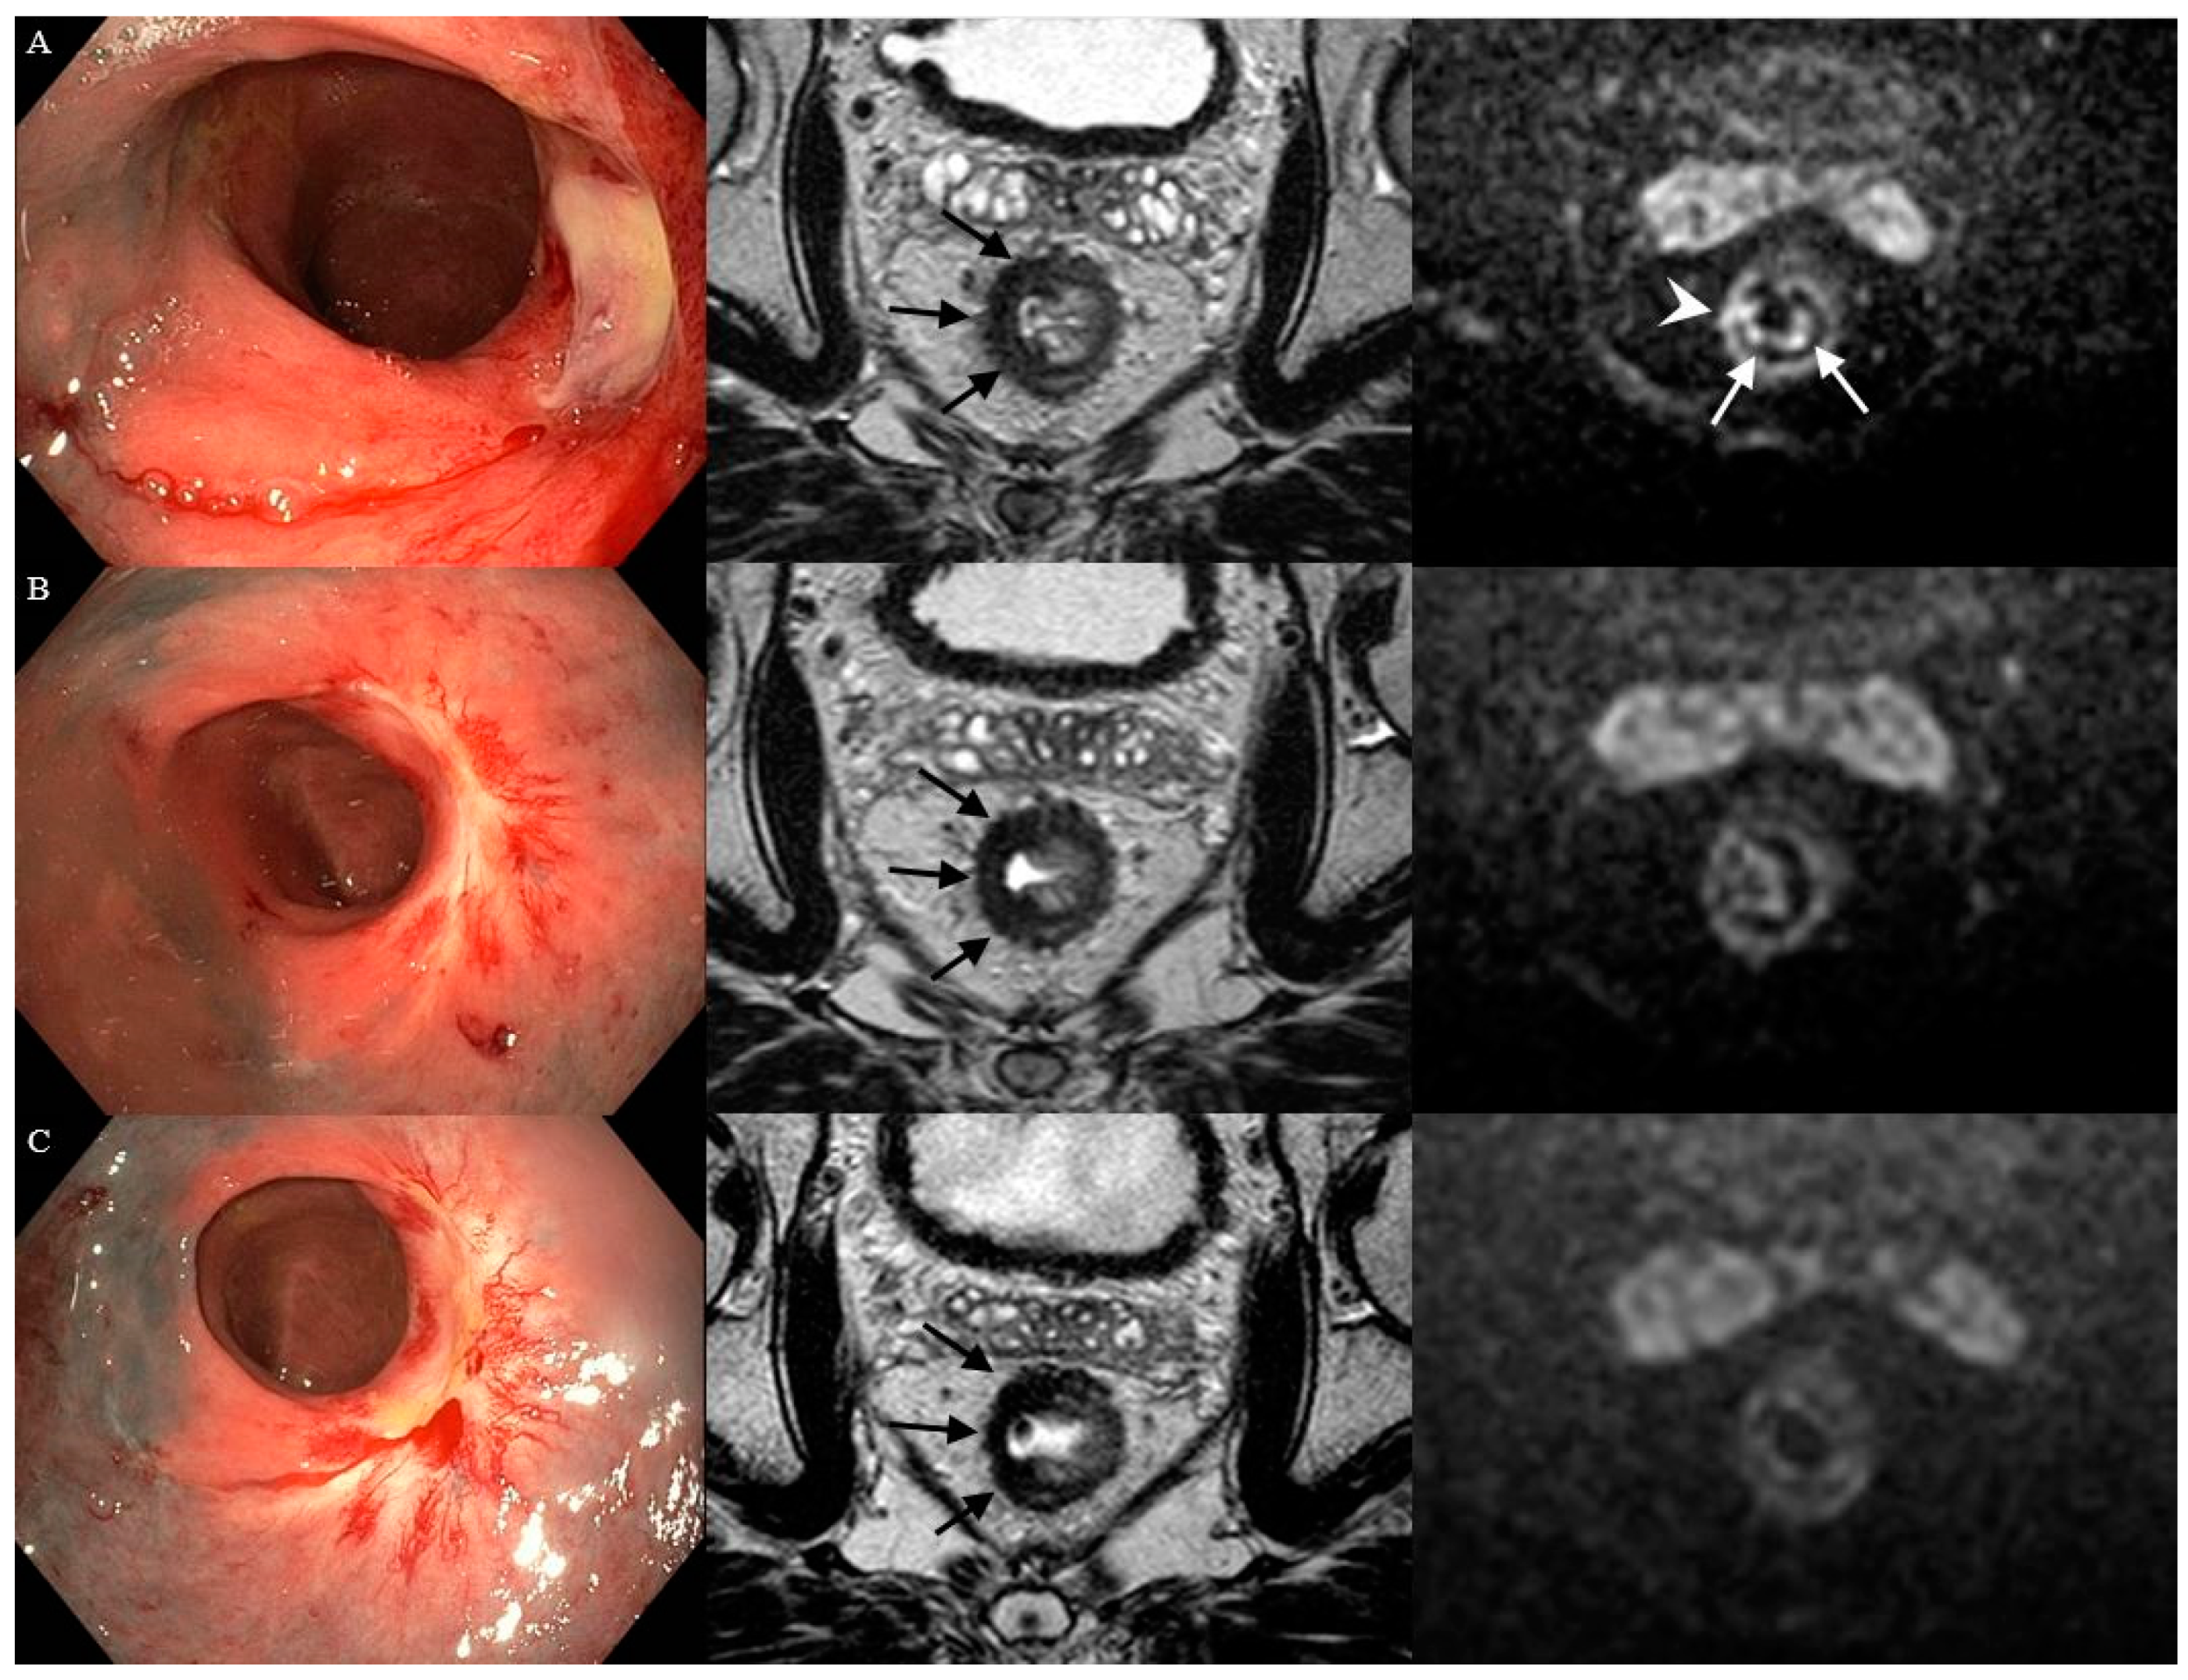

Figure 3.

Case of a healing ulcer on endoscopy and the presence of a more diffuse “reactive” mucosal signal on DWI after contact X-ray brachytherapy. Three months following CXB (A), an irregular ulcer on endoscopy, irregular heterogeneous fibrosis (black arrows) on T2W-MRI, and small focal spots of high signal within the fibrosis (white arrowhead) in combination with a diffuse “reactive” mucosal signal on DWI were observed. Later, during follow-up at 7 (B) and 11 (C) months, the ulcer on endoscopy healed into a flat, white scar, the fibrosis on T2W-MRI became more regular and homogeneous, and, on DWI, the small focal spots and the diffuse “reactive” mucosal signal disappeared.